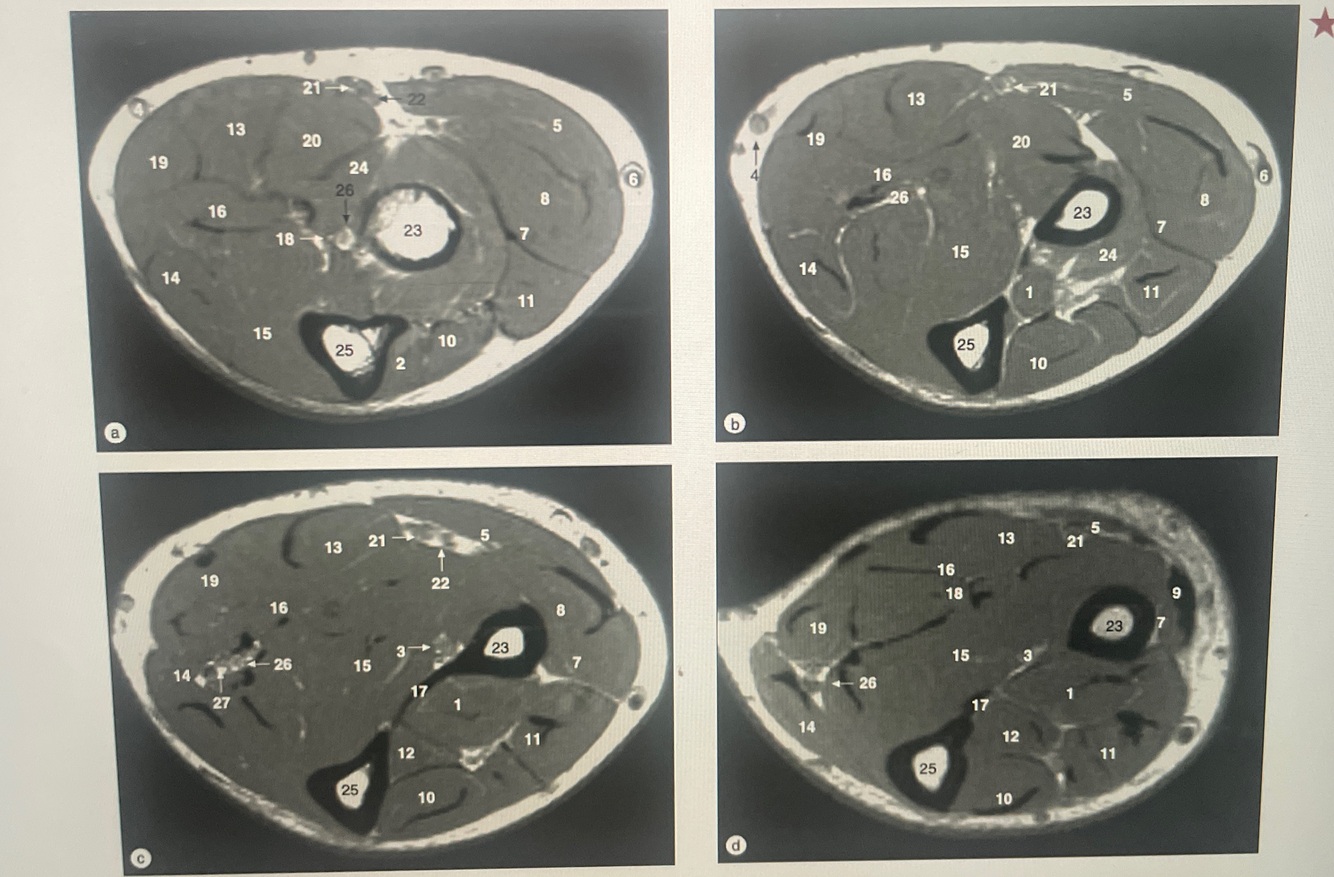

Identify